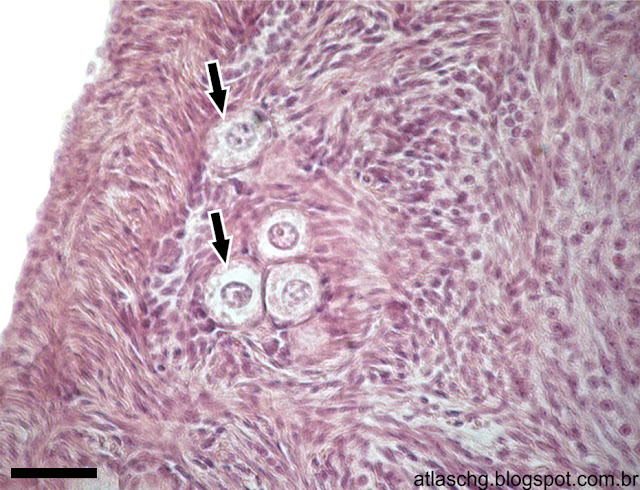

Corte de ovário. Folículos primordiais (setas), ampliados, situados na periferia do ovário. Coloração: Hematoxilina e Eosina (HE). Barra = 40µm.